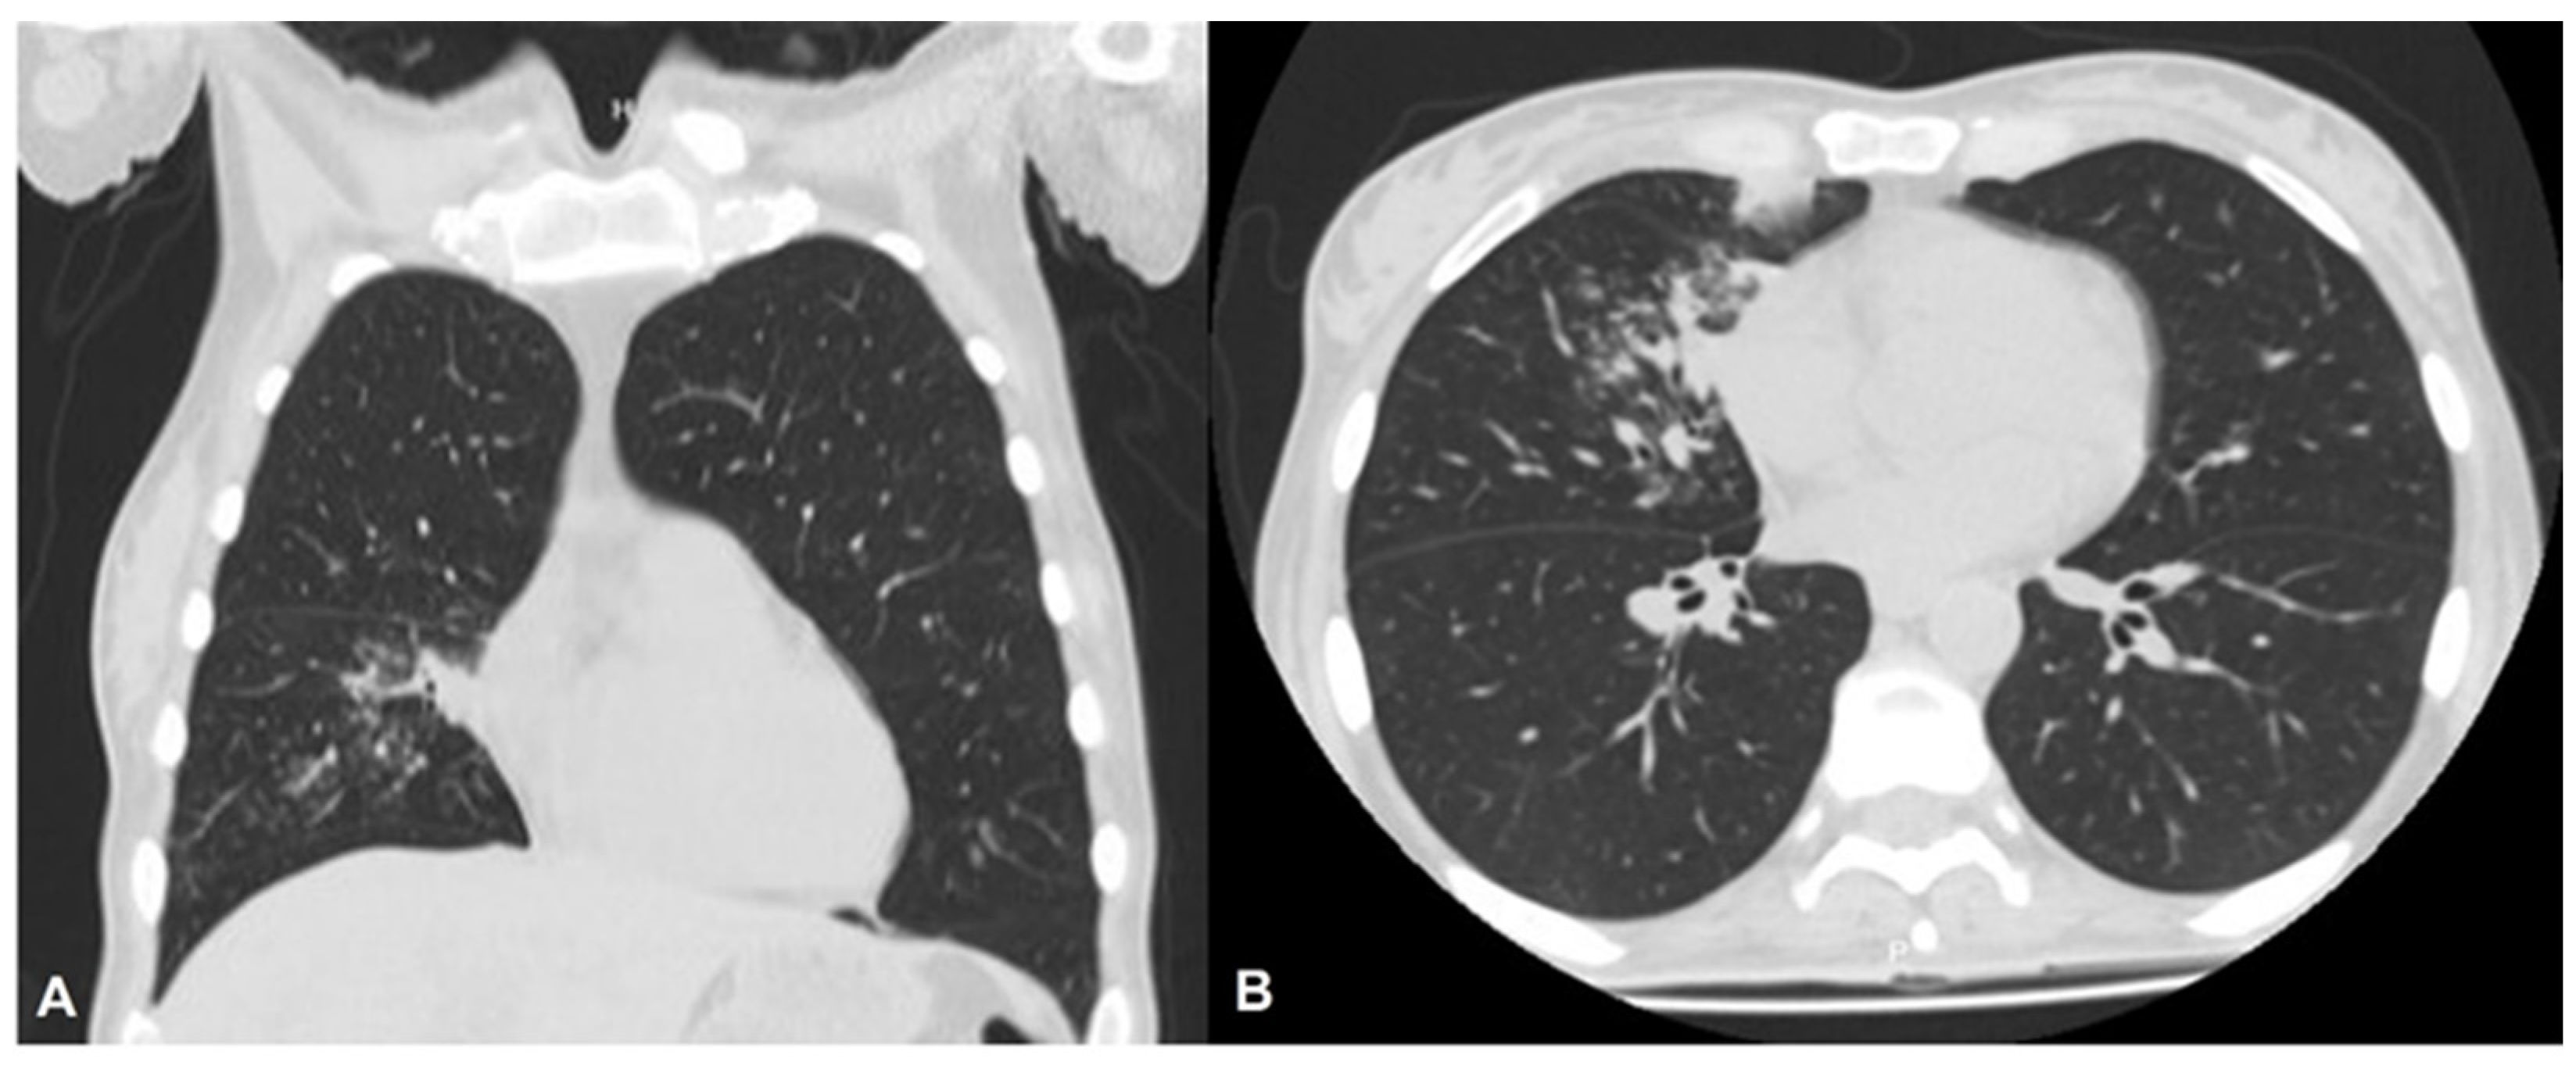

A 44-year-old HIV+ female attended a medical consultation in January 2021 with a cough that had been persisting for approximately 15 days. She was afebrile, with no diarrhoea, had a severe headache, and had experienced weight loss. The patient had a history of poor adherence to antiretroviral therapy (ART, 300 mg tenofovir, 200 mg emtricitabine, 300 mg atazanavir, and 100 mg ritonavir once daily) but declared adherence at the time of admission, which was well tolerated. She also declared that she consumed alcohol occasionally but neither consuming psychoactive substances nor smoking. She was first diagnosed with HIV in 2010 during pregnancy (viral load: 453,083 copies/mL; CD4+ count: 28 cells/mm3). At that time, the patient had a co-infection with Pneumocystis jirovecii and was therefore classified with an HIV infection at stage C3 (AIDS). She started ART at week three of gestation, achieving an undetectable viral load at the second trimester; however, she abandoned treatment soon after giving birth. She attempted to adhere to ART on several occasions afterwards but failed to comply with it repeatedly. Monitoring data on HIV infection status were available for October 2017 (viral load: 430,000 copies/mL; CD4+ count: 49 cells/mm3) and February 2019 (viral load: 61,982 copies/mL; CD4+ count: 269 cells/mm3). Lung function abnormalities compatible with tuberculosis were detected during a medical examination in January 2021 (Figure 1).

Figure 1.

High-resolution chest tomography. (A) Coronal cut of high-resolution chest tomography showing expanded lung parenchyma. (B) Transversal cut of high-resolution chest tomography showing lung centrilobular nodules with a budding tree pattern, mainly in the middle lobe and a few in the left apical.

Chest radiography did not show signs of an increased cardiothoracic ratio or pulmonary congestion. Sputum smear microscopy was negative for alcohol-acid-resistant bacilli; the Xpert® MTB/RIF PCR assay was negative for rifampicin-resistant Mycobacterium complex species; and no mycobacterial growth was observed in Löwenstein–Jensen and MGIT solid media for as long as eight weeks. Antigen detection for Histoplasma capsulatum was negative. HIV infection status revealed a viral load of 625,664 copies/mL and a CD4+ count of 23 cells/mm3, which is strongly suggestive of medication non-adherence.